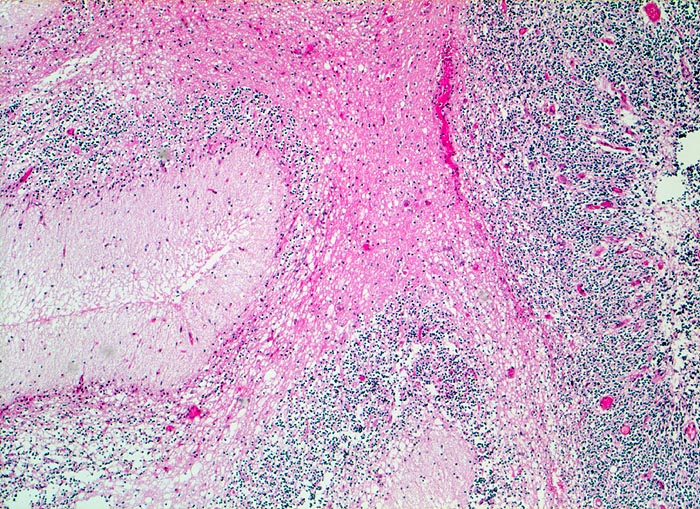

Schlecht erhaltenes Kleinhirn angrenzend an das Medulloblastom (in diesem Bild nicht sichtbar). Kleinhirnmark, Stratum moleculare und Körnerschicht der Kleinhirnrinde.

Medulloblastom angrenzend an das Kleinhirn und die Medulla oblongata

Knabe mit Kopfschmerzen und morgendlichem Erbrechen ohne Übelkeit

Histologie

50